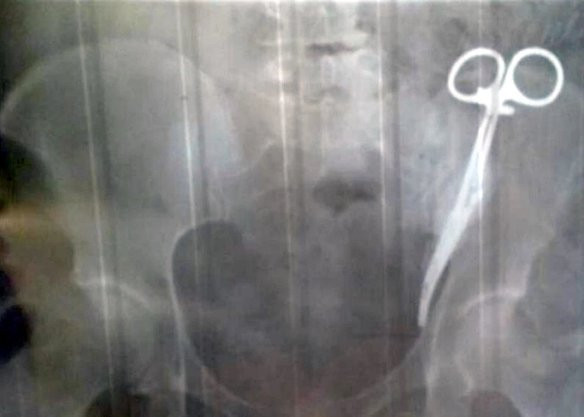

Bà Ezeta Gobeeva cùng hình ảnh phim chụp X-quang khoang bụng của mình.

Trong lần đi khám ở bệnh viện gần đây, nhờ sự trợ giúp của công nghệ chụp X-quang, các bác sĩ phát hiện một chiếc kéo y tế dài khoảng 15cm nằm trong bụng bà. Đây chính là thủ phạm gây ra những cơn đau bụng cấp tính cho bà Gobeeva suốt thời gian dài.

Chiếc kéo bị bỏ quên trong bụng của bà Gobeeva.